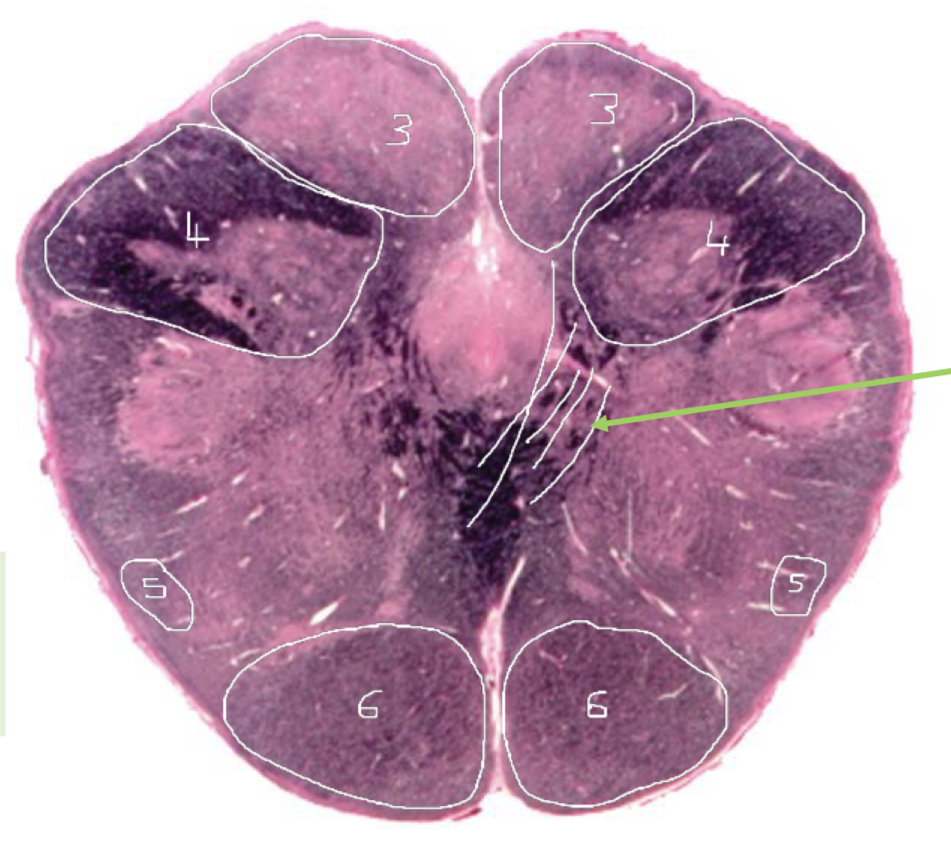

1

Medial Lemniscus - Caudal Pons

2

Spinothalamic Tract - Caudal Pons

3

CST - Caudal Pons

4

4th Ventricle - Caudal Pons

5

Inferior Cerebellar Peduncle - Caudal Pons

6

Middle Cerebellar Peduncle - Caudal Pons

7

Superior Cerebellar Peduncle - Caudal Pons

8

Dentate Nuclei (Cerebellum) - Caudal Pons

9

Inferior Olivary Nucleus - Caudal Pons

10

Medial Longitudinal Fasciculus (MLF) - Caudal Pons